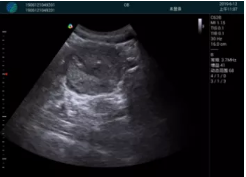

M20查看:囊內回聲均勻,邊界清晰,囊壁光滑

M20引導抽吸術(shù)后囊腫消失,原區域空腔形成,脂肪層與腺體層架構發(fā)生改變